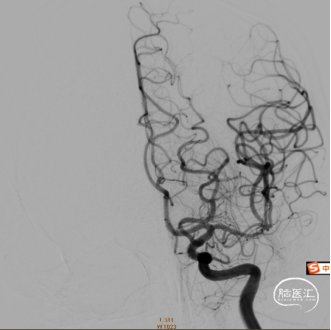

造影可见左侧颈总动脉闭塞、左侧大脑中动脉通过前交通向左侧大脑供血。

通过6F抽吸导管应用50ml注射器负压抽吸出大量暗红色血栓后,造影可见左侧颈内动脉后交通段显影。

再次应用6F抽吸导管抽吸,仍有少量暗红色血栓抽出,造影可见左侧大脑前动脉及左侧大脑中动脉。大脑动脉M1远段未见显影(血栓逃逸)。

输送微导丝微导管小心通过闭塞段,微量造影,远端血管显影,回撤微导丝后推送并释放4x30mm Syphonet®取栓支架,可见Syphonet®取栓支架清晰显影,支架打开良好。

Syphonet®取栓支架应用SWIM技术抽拉结合取栓一次,造影确认脑血流完全恢复,mTICI 3级,成功一把再通。